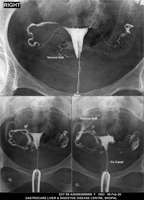

Section: HSG

Total: 49 Cases

All Categories BaM Enteroclysis Loopogram BaE Fistulogram Urethrogram HSG